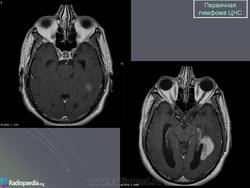

Первичные лимфомы ЦНС. Вс, 22/05/2011 - 21:45 #1 Катенёв Валенти... Не на сайте Был на сайте: 7 лет 5 месяцев назад Зарегистрирован: 22.03.2008 - 22:15 Публикации: 54876 Продолжение.Приложения: